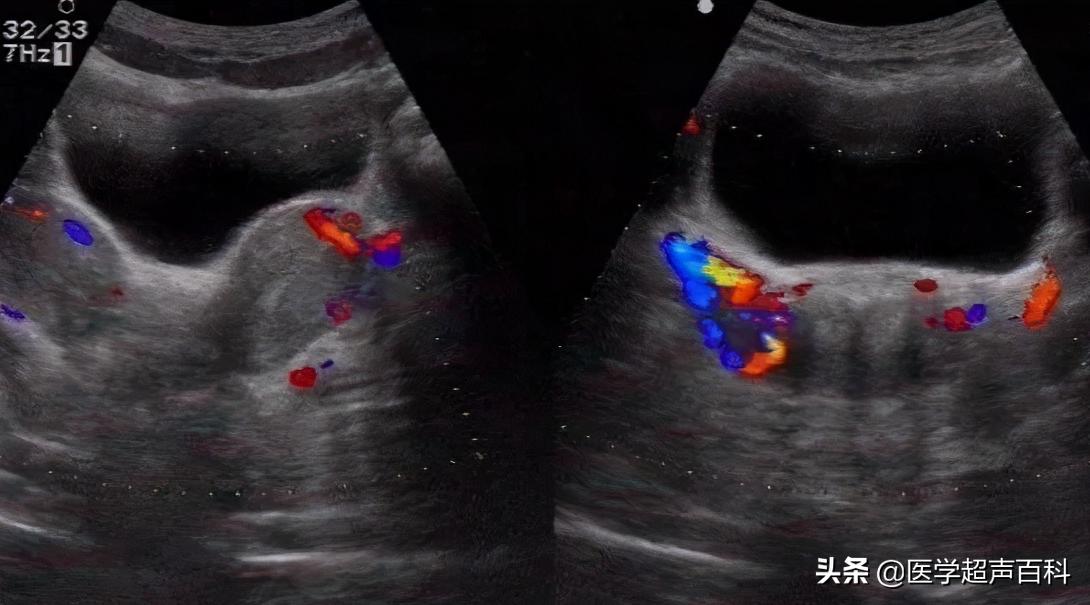

4.双子宫:连续纵切面扫查可见先后显示两个狭长的子宫。宫体及宫底横切面,可显示左右对称的两个子宫,两个子宫均可见各自的内膜回声;宫颈横切面见宫颈横泾增宽,可见两个宫颈管回声。可见双侧卵巢影像。